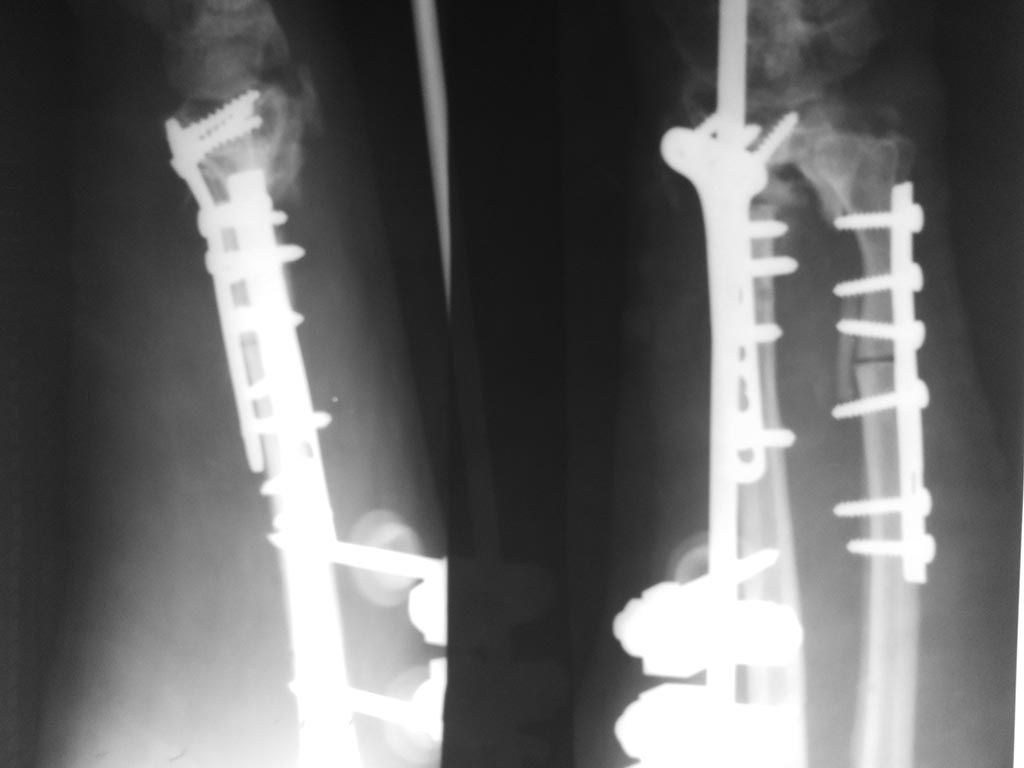

Спасибо за помощь. Результаты оперативного лечения.